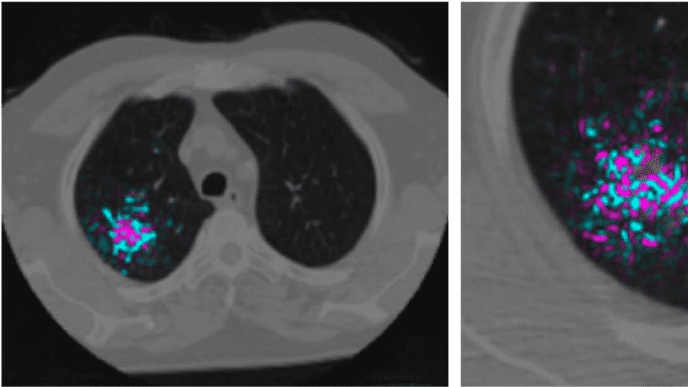

مصدر الصورة: مجلة نيتشر

قام دانيال تسي، أحد الباحثين لدى جوجل، بتطوير خوارزمية تغلبت على مجموعة من اختصاصيِّي الأشعة المتمرسين في مجال تشخيص سرطان الرئة. حيث درّب الباحث دانيال وزملاؤه خوارزميةَ تعلمٍ عميقٍ على اكتشاف العُقيدات الرئوية الخبيثة (المصابة بالسرطان) في أكثر من 42,000 فحص مقطعي محوسب (CT scans). وأسفرت التجارب عن اكتشاف الخوارزميات المدرّبة لنتائج إيجابية كاذبة بنسبة 11% أقل من اختصاصيِّي الأشعة البشر، ونتائج سلبية كاذبة بنسبة 5% أقلّ منهم أيضاً. ويُذكر أن هذه التجارب سُرِدت في ورقة علمية محكمة نشرت في مجلة "نيتشر" العلمية.